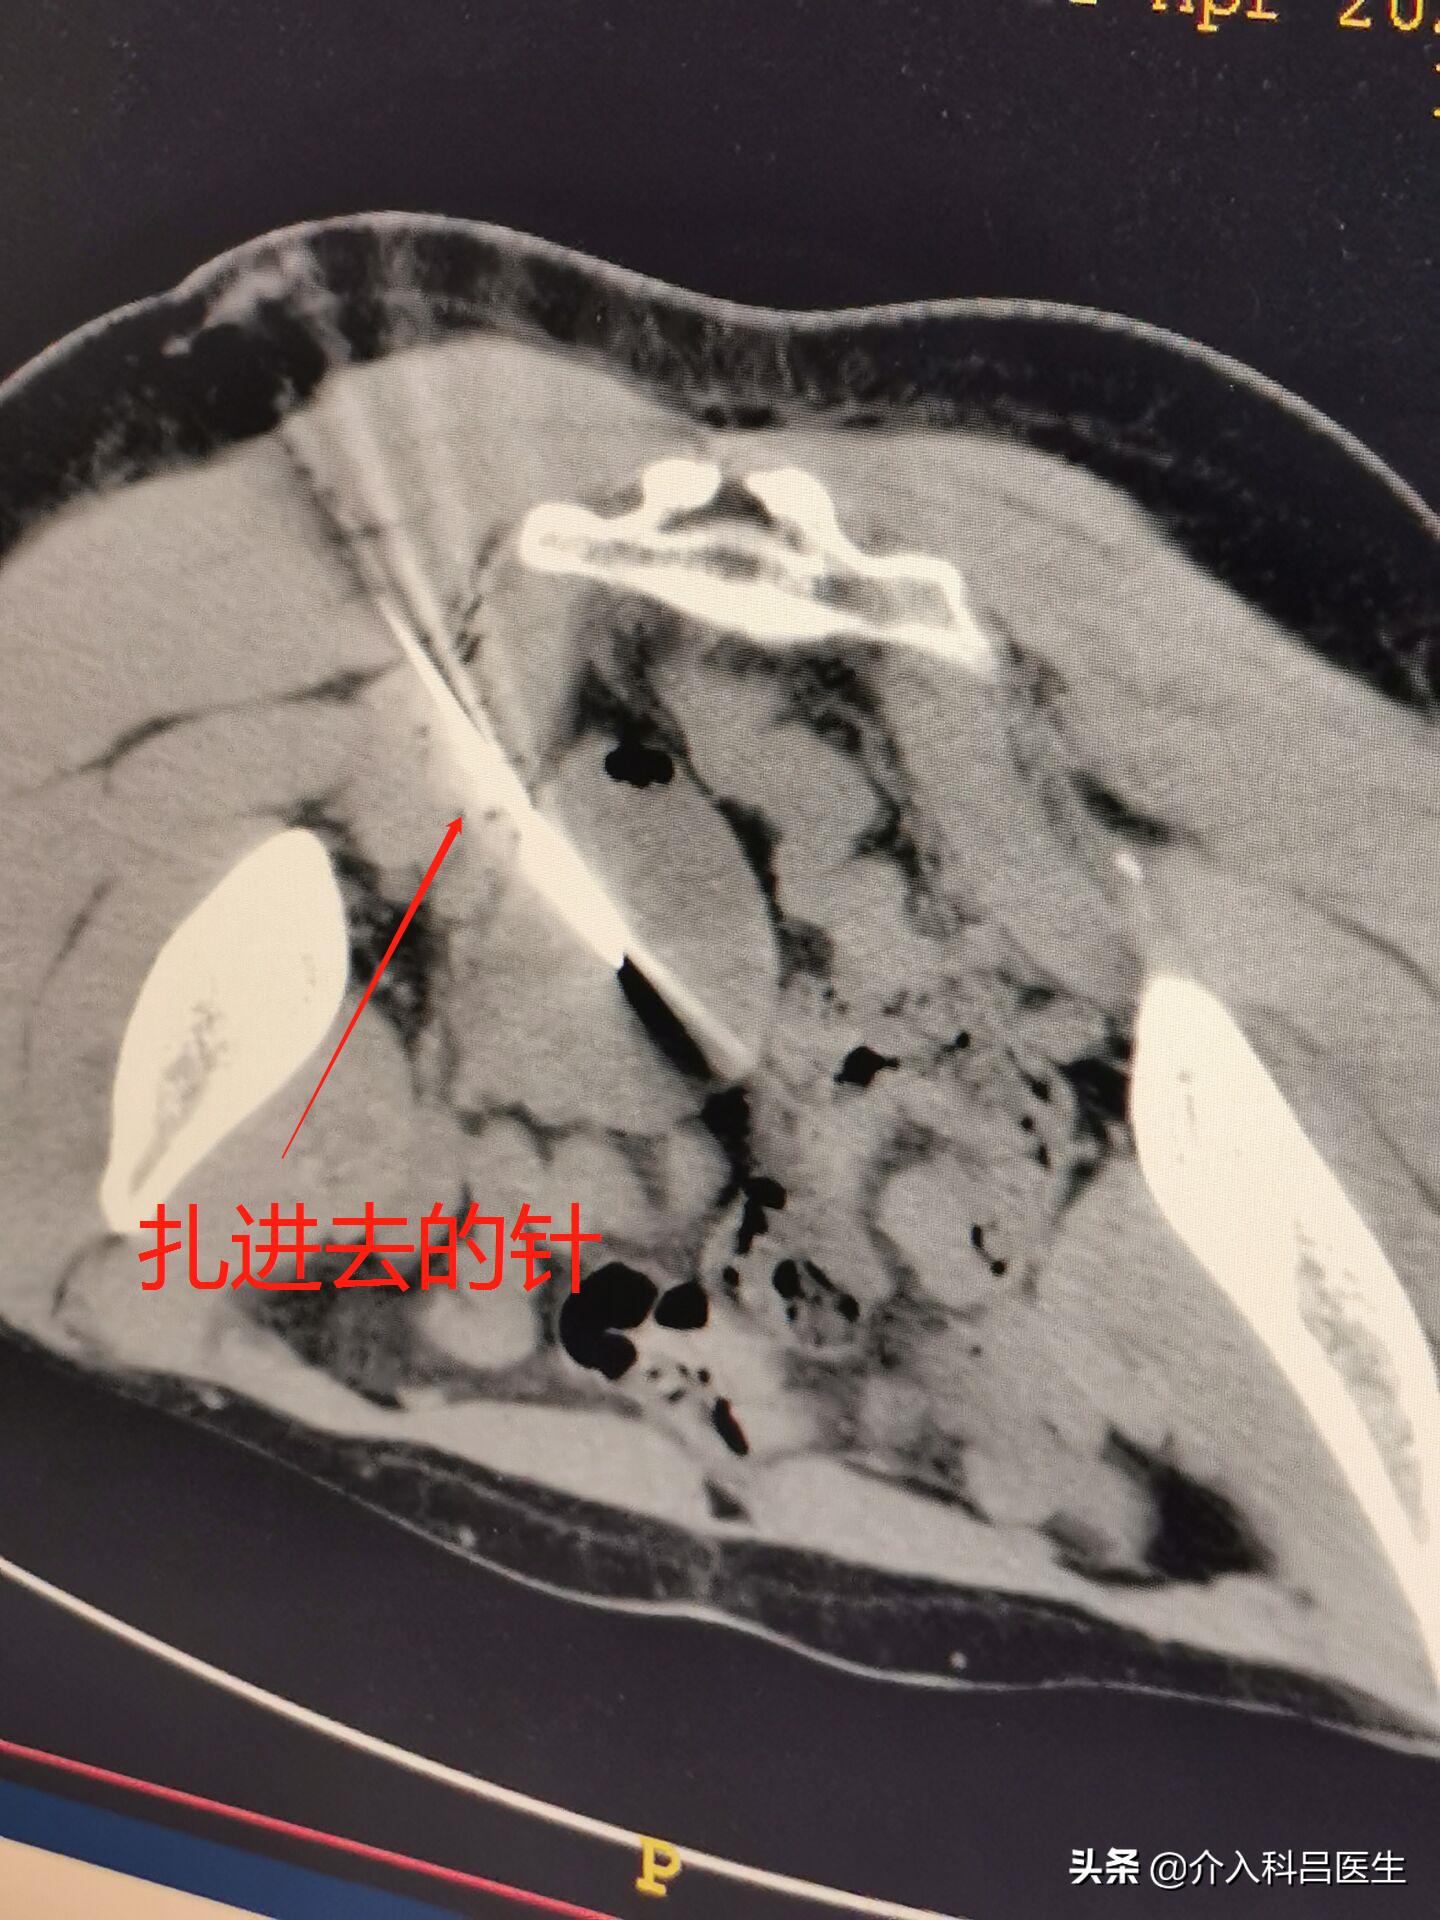

患者年前就关注了我,今年大老远跑过来,坐高铁还要3个小时,一定要我亲自做,那我也不能辜负大家的信任。手术在ct引导下操作,一根针扎进去,在ct上观看位置特别好,正中囊肿中心,然后将里边的囊液抽出来。下图是抽出来的囊液,是不是很像巧克力?

ct显示下的针